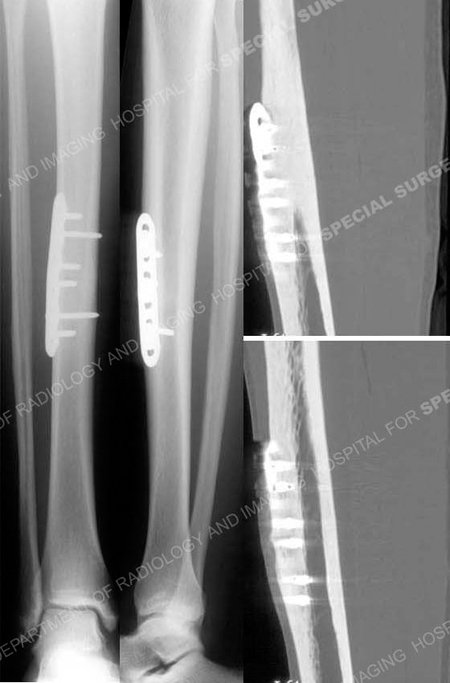

Anteroposterior and lateral radiographs (left images) 8 months following surgery revealing a healed tibia stress fracture and CT scan images (right images) at 8 months illustrate a healed tibial stress fracture.